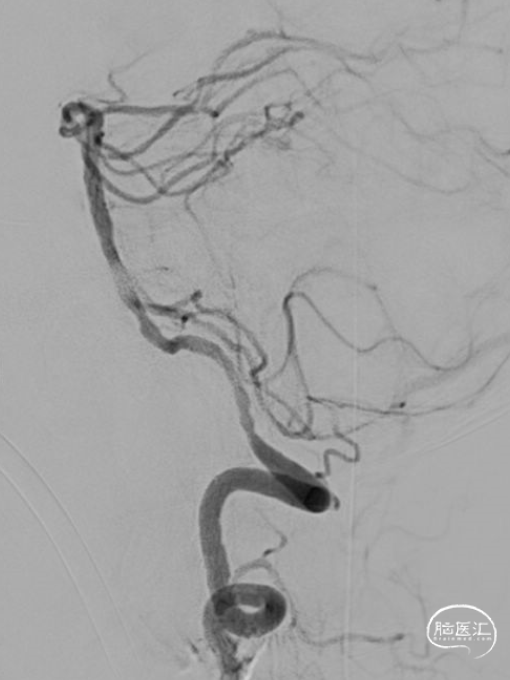

术前DSA示:右侧椎动脉及左侧椎动脉V2段未见显影;基底动脉未见显影。

微导管造影示左椎V4段闭塞,Synchro-14 300cm微导丝携带泰杰伟业-16 150cm微导管小心前行通过左侧椎动脉V4闭塞段,导丝前行至基底动脉起始段,微导管跟至此段,撤出微导丝,手推造影证实基底动脉近段狭窄,血流通畅。

Acandis支架 4.5*30释放,再次造影证实左侧椎动脉V4段血栓影,计时5分钟,50ml注射器负压抽吸中间导管,行抽拉结合取栓一次,可见少许碎小血栓取出,再次造影证实左侧椎动脉V4段大量血栓影。

Neuron MAX跟至左椎V1段,中间导管跟至V3段,撤出泥鳅导丝,关闭所有前向冲洗。50ml注射器负压抽吸中间导管小心前向,可见大量血栓取出,再次造影证实左侧椎动脉血流通畅,远端血流缓慢。

动脉团注替罗非班5ml,注入后远端血流改善,左侧椎动脉V4段及基底动脉近段局限性狭窄。依次撤出导管组合,手术结束。